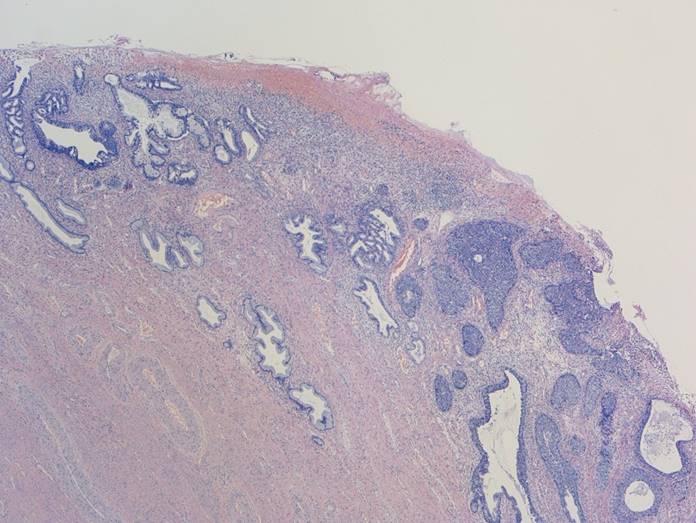

組織所見

子宮頸部のSCJにおいてクロマチン増量を示す異型上皮が明瞭な

腺管構造や充実性胞巣構造を形成し増生していた。充実性増生を示す成分はN/C比や核分裂像が目立ち、免疫染色ではsynaptophysin、chromogranin A、CD56が陽性であり神経内分泌分化が示唆された。以上の所見より、神経内分泌癌成分を伴う腺癌と診断された。面積的には腺癌成分が8割で神経内分泌癌成分は2割であった。腺癌成分で微小浸潤がみられたが神経内分泌癌成分はin situであった。

腺管構造や充実性胞巣構造を形成し増生していた。充実性増生を示す成分はN/C比や核分裂像が目立ち、免疫染色ではsynaptophysin、chromogranin A、CD56が陽性であり神経内分泌分化が示唆された。以上の所見より、神経内分泌癌成分を伴う腺癌と診断された。面積的には腺癌成分が8割で神経内分泌癌成分は2割であった。腺癌成分で微小浸潤がみられたが神経内分泌癌成分はin situであった。